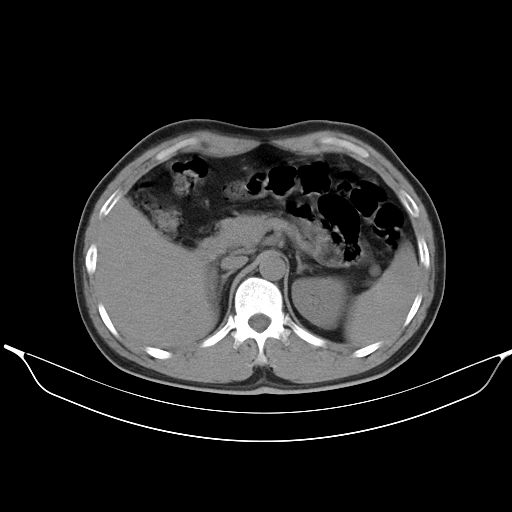

标题: CT25490:男,40岁,体检发现;无其它不适。 [打印本页]

标题: CT25490:男,40岁,体检发现;无其它不适。

转移性肺肿瘤不排除,建议结合相关检查考虑

1、均为转移,原发灶不在肺内。2、肺癌肺转移。